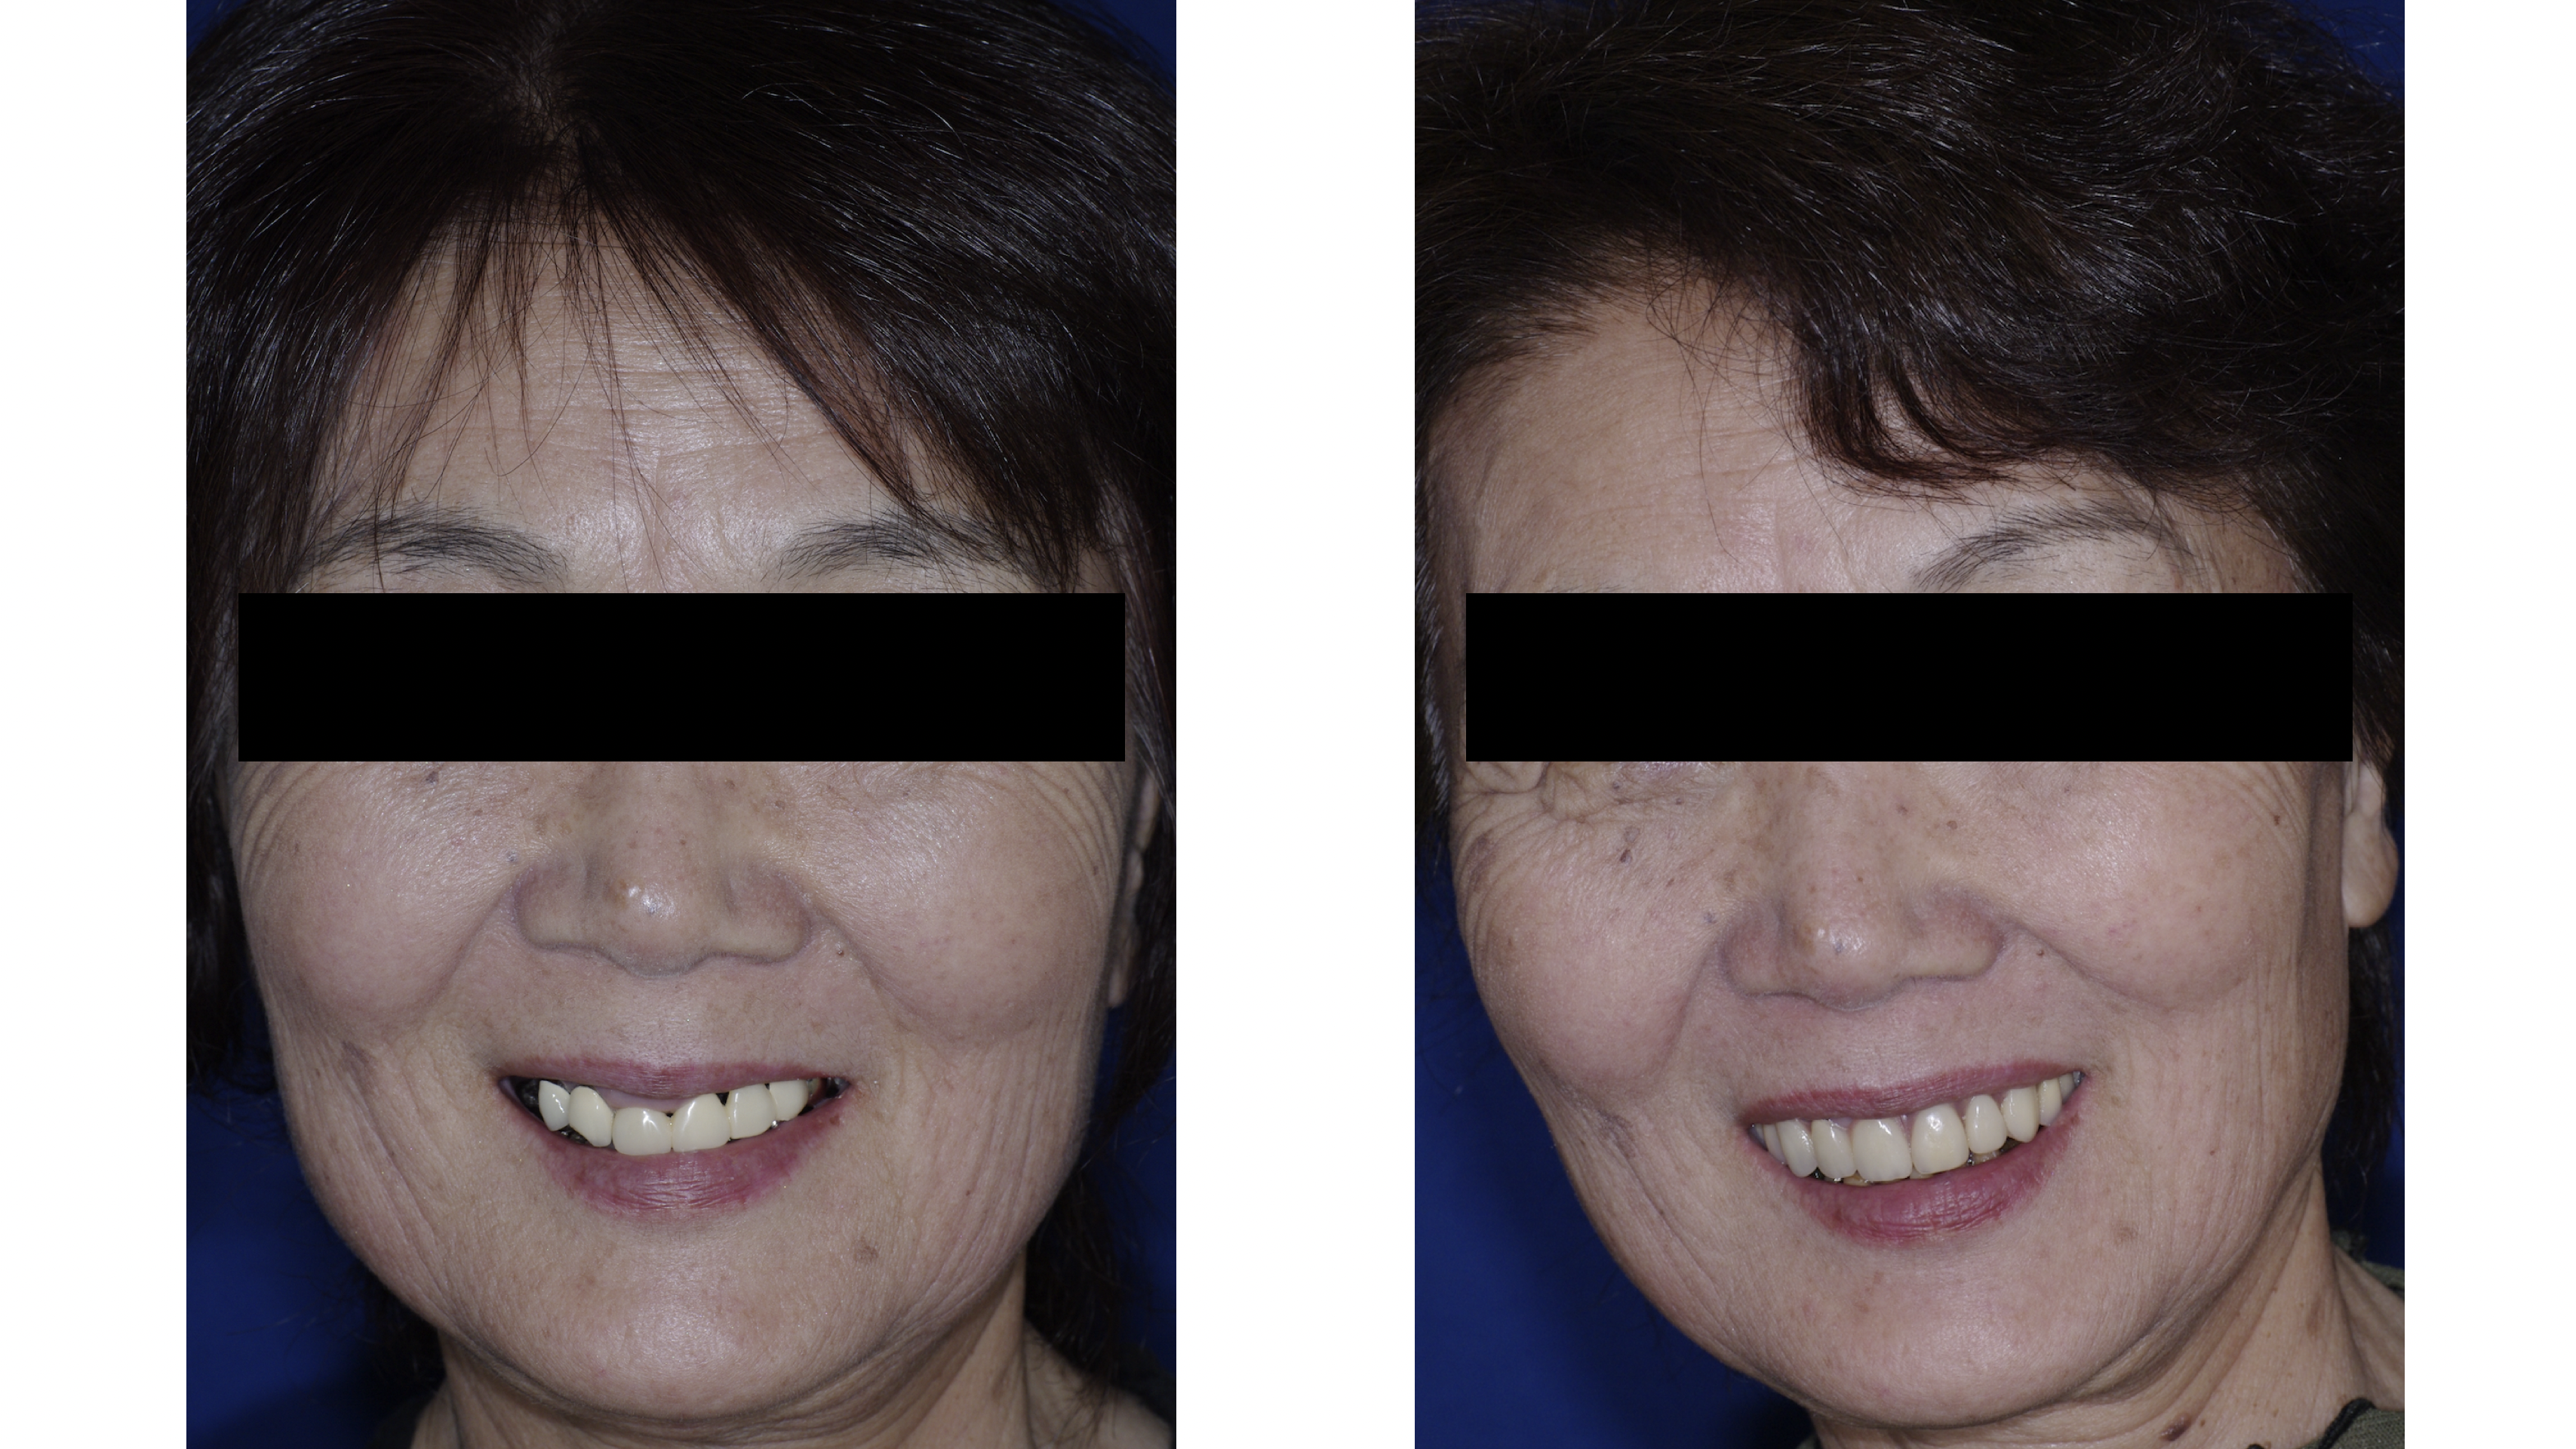

口元は美しく ごきげんに

機能が改善されると審美性も改善されます。

美しい口元で会話が弾みます。

健康寿命を伸ばす強力な要素の1つは社会性です。

素敵な仲間と楽しい時間を!

美しい口元で会話が弾みます。

健康寿命を伸ばす強力な要素の1つは社会性です。

素敵な仲間と楽しい時間を!